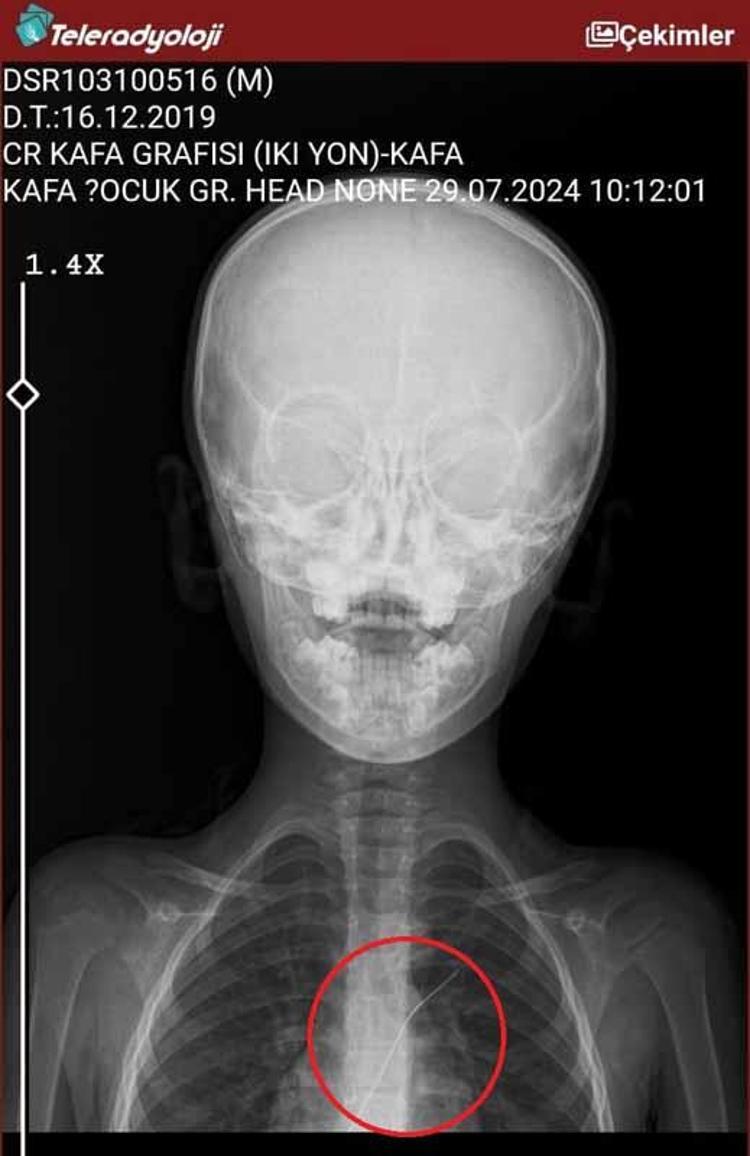

Şırnak’ta piknikte salatalık parçası yuttuktan sonra öksürük ve kusma şikayetleriyle hastaneye götürülen Aram Devran Ötün’ün (6), 3 yıl önce Stevens- Johnson sendromu nedeniyle tedavi gördüğü sırada damar yoluna takılan 18 santimetrelik kateterin vücudunda unutulduğu ortaya çıktı. Öğüt, 5,5 saat süren riskli bir ameliyatla kateterden kurtuldu.

Şırnak’ta yaşayan Semra (37) ve Mehmet Ötün (40) çiftinin oğulları Aram Devran Ötün, mayıs ayında piknikteyken salatalık parçası yuttuktan sonra öksürük ve kusma şikayetleri görülünce Şırnak Devlet Hastanesi’ne götürüldü. Burada çekilen röntgen ve MR’da Aram’ın vücudunda kateter unutulduğu görüldü. Diyarbakır’daki Gazi Yaşargil Eğitim ve Araştırma Hastanesi Kadın Doğum ve Çocuk Ek Binası’na sevk edilen Aram, 5,5 saat süren riskli bir ameliyata alınarak 18 santimetre uzunluğundaki kateter çıkarıldı. Ameliyat sonrası yapılan incelemelerde kateterin kalp kapakçığına ve ciğerlerine zarar verdiği belirlendi.

Ailenin avukatı Ahmet Yalçın, hastane hakkında hem şikayetçi olduklarını hem de dava açtıklarını belirterek, “Müvekkilim Aram Devran Ötün, 2022 Eylül ayında Dicle Üniversitesi Hastanesi’nde Stevens- Johnson hastalığı nedeniyle tedavi gördü. Tedavi sırasında kendisine kateter takıldı. 18 santimetre uzunluğundadır. Bunu takarken büyük bir ihmalkarlık yapılarak vücudunda unutuldu. Mayıs ayında müvekkilim çok öksürdüğü için Şırnak Devlet Hastanesi’ne kaldırıldı. Burada yapılan tetkiklerde kateterin unutulduğu tespit edildi. Daha sonra Diyarbakır Gazi Yaşargil Kadın ve Çocuk Hastalıkları Hastanesi’ne götürüldü. Çok riskli bir ameliyata alındı ve kateter çıkarıldı. Bu kateterin vücutta yol aldığı tespit edildi. İlk giriş yeri ve çıkarıldığı yer arasında çok fark var ve kalp kapakçığı ile ciğerlerine zarar verdiği tespit edildi. Müvekkillerimin hem maddi hem de manevi zararlarını karşılamak adına Dicle Üniversitesi’ne biz başvuruda bulunduk. 30 günlük cevap süresi içerisinde bize geri dönüş yapılmadı. Biz de maddi ve manevi zararların tazminat için Diyarbakır İdare Mahkemesi’ne davamızı açtık ve sorumlulardan şikayetçi olduk” dedi.

Oğlunun piknikte salatalık parçası yuttuktan sonra sürekli öksürmeye ve kusmaya başladığını söyleyen Semra Ötün, “Çocuğum 3 yıl önce Steven Johnson sendromu hastalığına yakalandı. Milyonda bir görülen antibiyotikten kaynaklı bir hastalık. Doktorlar öyle söyledi. Bizi acilen Diyarbakır Dicle Üniversitesi Çocuk Hastanesi bölümüne sevk ettiler. 1 ay yoğun bakım sürecimiz oldu. 28 gün yoğun bakımda, 3 günde serviste kaldı. Damar yolundan, kasıktan serum taktılar. Kateter denilen tel çocuğun vücudunda bırakılıyor. Biz taburcu olduğumuzda fark edilmiyor. 3 yılın sonunda biz bunu fark ettik. Pikniğe gittik. Oğlum salatalık parçası yuttu ve salatalık parçasından sonra akşama kadar öksürdü. Hiçbir şekilde durmadı. Kusuyordu. Ben şüphelenmeye başladım. Çocuğum normal değildi. Sonra eşime danıştım. Akşam 21.00 civarında acile götürdük. Röntgeni ve MR’ı çekildi. Tuhaf bir şey olduğunu anladık. Doktor röntgeni gösterdi. Tel kalmıştı. Çok kötü bir şekilde. Acil doktoru film çektikten sonra bize bir tel parçasını gösterdi. Bizi bekletmeden Diyarbakır’a sevkimizi verdiler. Diyarbakır Gazi Yaşargil Eğitim ve Araştırma Hastanesi Kadın Doğum ve Çocuk Ek Binası’na gittik. Çocuğun kasıklarından anjiyo yolu ile teli çıkaracaklarını ama riskli bir ameliyat olduğunu söylediler. O süreçte çocuk gerçekten sürekli yoruluyordu. İkide bir oturuyordu. ‘Anne çok yoruldum, karnım ağrıyor’ diyordu. Ben ağrı kesiciler ile geçiştirmeye çalışıyordum. Bu telin 3 yıl boyunca çocuğumda kaldığını öğrendim. Ailece yıkıldık” diye konuştu.